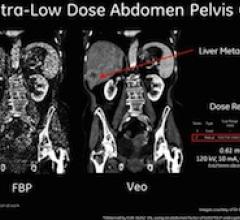

October 20, 2011 – GE Healthcare’s CT and Advantage Workstation team at RSNA 2011 will showcase innovative new products and technologies that may enable physicians to diagnose more confidently while improving image clarity, reducing patient dose and enhancing workflow.

Minimizing X-ray dose has driven the global imaging community to develop technologies that today can cut patient dose from computed tomography (CT) to a fraction of its previous levels. So it may soon be in mammography.